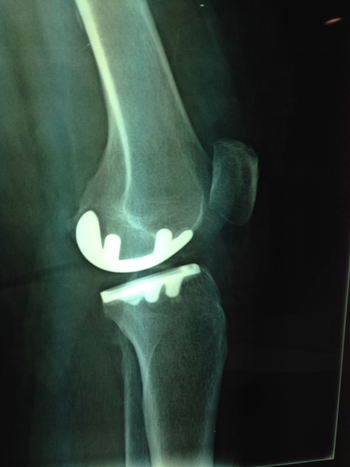

| Οστεοαρθρίτιδα γόνατος (προεγχειριτική) | Οστεοαρθρίτιδα γόνατος (μετεγχειριτική) |